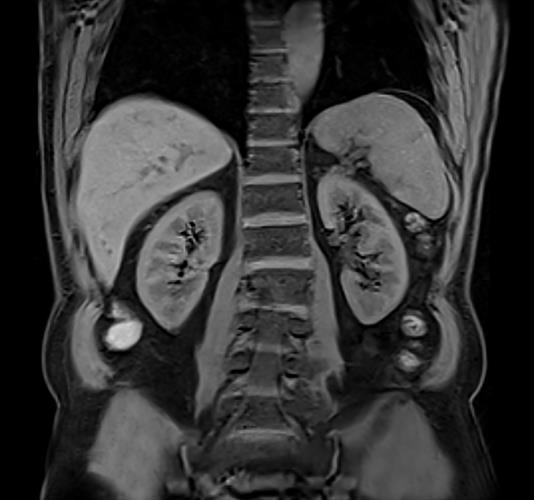

Good results are obtained by MRI in the study of internal organs :

- abdominal and retroperitoneal space: kidney, liver, pancreas, bile, adrenal glands, spleen;

Examination of the abdominal organs includes the study of the spleen, gallbladder and ducts, pancreas, kidneys and adrenal glands.During the procedure, doctors can detect the following diseases of internal organs :